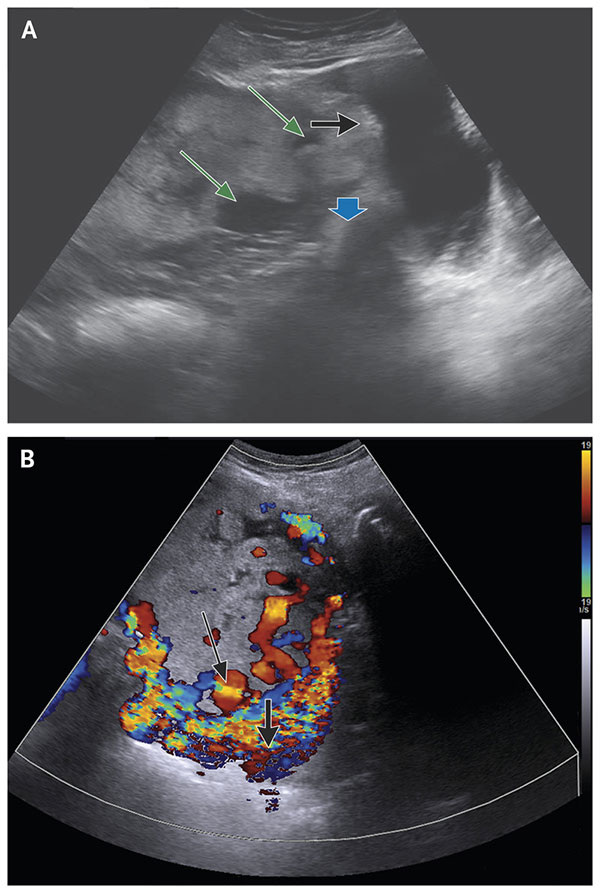

سنگ کیسه صفرا چطور تشکیل میشود و درمان آن چیست؟

تصویربرداری

1404/11/29

سنگ کیسه صفرا زمانی تشکیل می شود که موادی مانند کلسترول یا بیلی روبین در صفرا (ماده ای که توسط کبد تولید و در کیسه صفر...